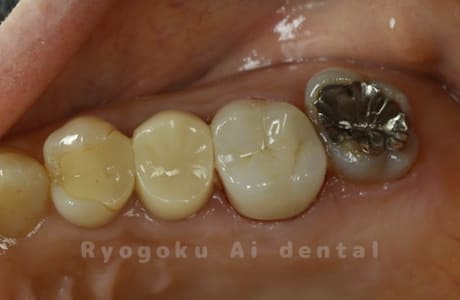

Case11

- インレー2次カリエス、ならびにインレー脱離

- 治療内容

- 123,000円×2(セラミッククラン)、77,000円(セラミックインレー)

銀歯が取れて、ご来院された患者様です。奥歯2本をセラミッククラウン、手前の小臼歯をセラミックインレーで治療を行いました。

<リスク・副作用>

過度の咬合や衝撃で割れることがあります。